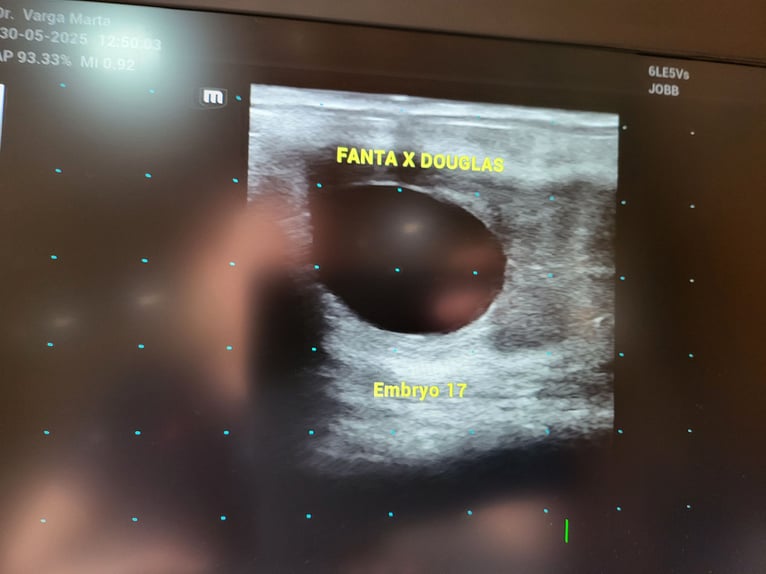

jest źrebna

Our horse named Fanta was born with us from excellent parents. She has a very lovable and friendly nature, making her an ideal choice for beginners or a family favorite. Her training has already started: she can be bridled, saddled, and we've already ridden her on a lunge line. She is a well-moving horse with a beautiful appearance and is being sold with Douglas's approval. She is an ideal choice for both beginner and advanced riders looking for a reliable and kind companion. Please feel free to contact us for inquiries and viewings! (Zapatero VDL, Sixtus, Solero)